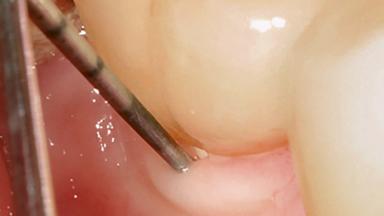

Treatment of Peri-Implant Mucositis at a Zirconia Implant

Recent clinical studies, most with short-to-medium term observation periods, have reported on the favorable clinical performance of zirconia implants in terms of survival rates, clinical, and radiographic outcomes (Roehling and coworkers 2016; Roehling and coworkers 2017; Rodriguez and coworkers 2018; Lorenz and coworkers 2019). Nonetheless, a rather high incidence of peri-implant disease at zirconia implants (39% of implants) was noted throughout a two-year period, highlighting the need for treatment protocols of peri-implant diseases at zirconia implants (Becker and coworkers 2017).